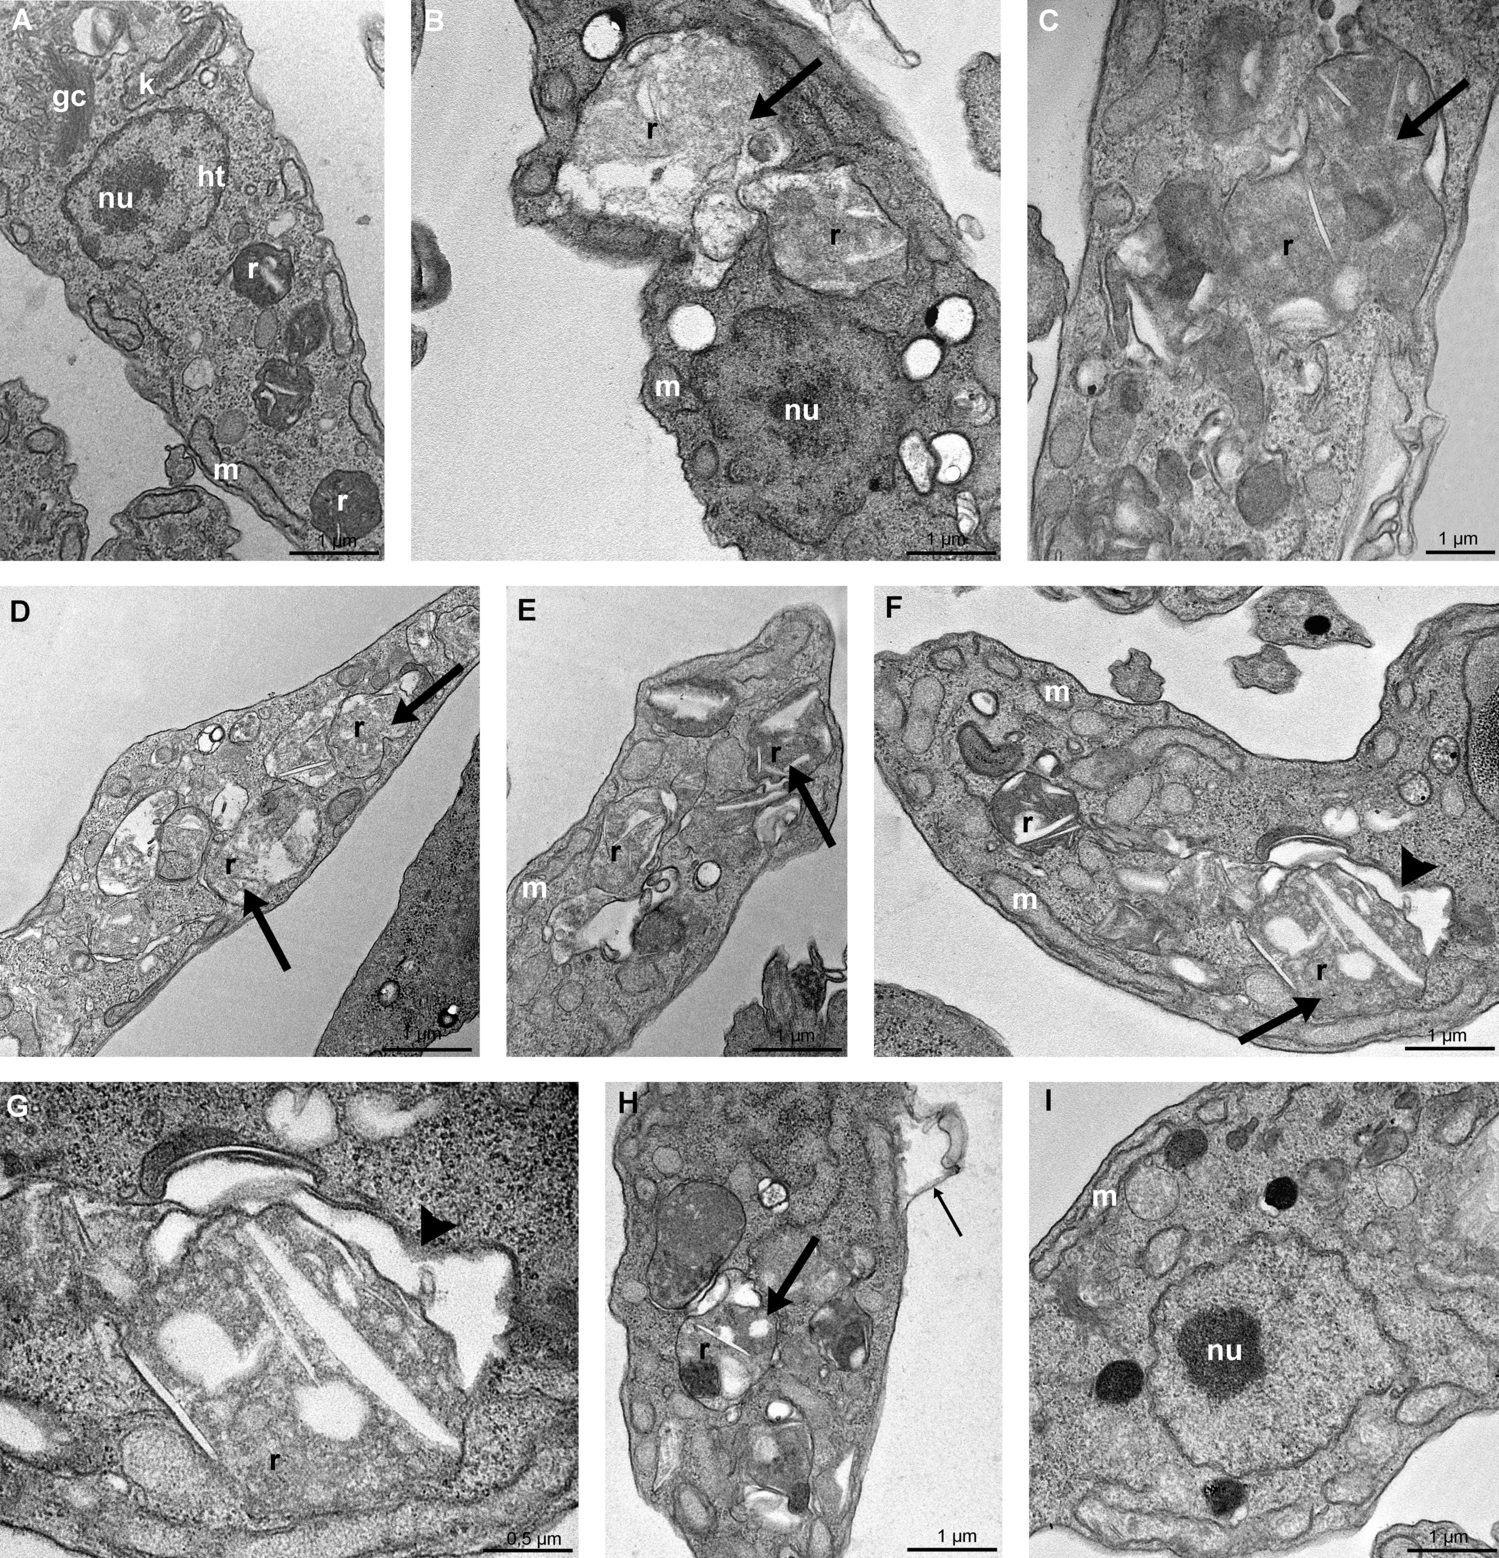

Figure 5

Transmission electron microscopy of T. cruzi epimastigotes in the presence of FEX for 72 h. (A) Non-treated epimastigote with the Golgi complex (GC) near the bar-shaped kinetoplast (k), the nucleus with the condensed heterochromatin (ht) close to the nuclear envelope and around the nucleolus (nu), a single branched mitochondrion (m) and reservosomes (r) at the posterior end. (B–E) Treatment with 20 µM (B, C) and 30 µM (D, E) caused a loss of rounded shape and matrix content of the reservosomes (thick arrow). (F–I) Treatment with 40 µM also caused the detachment of the reservosomes from the cytoplasm (F, G, arrowhead), detachment of the plasma membrane (H, thin arrow), and the unpacking of nuclear heterochromatin (I).